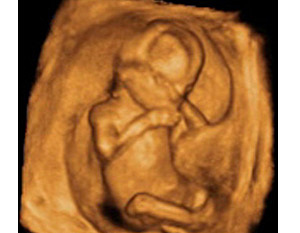

La ecografía puede decirnos muchas cosas: si hay malformaciones graves, si falta alguna extremidad, o incluso adelantar el sexo del bebé, porque ya están formados los genitales externos. La embarazada suele entrar en una etapa de mayor estabilidad (menos náuseas y vómitos) a medida que su útero crece.La cabeza sigue ocupando la mitad de la longitud embrionaria. Aparecen barbilla y cuello a medida que la cabeza se va separando del pecho. Empiezan a diferenciarse las uñas de los dedos.

El peso del feto oscila entre 8 y 14 gramos y mide entre 5 y 6 centímetros desde la cabeza al coxis.Los huesos tienen unos centros de osificación que les permiten ir creciendo. Los dedos de manos y pies están separados unos de otros y tienen movimiento.

Las uñas están creciendo y aparece el primer vestigio de pelo en todo su cuerpo. El sistema nervioso fetal está desarrollándose y la hipófisis está segregando muchas hormonas. El intestino delgado es capaz de contraerse para transportar la comida